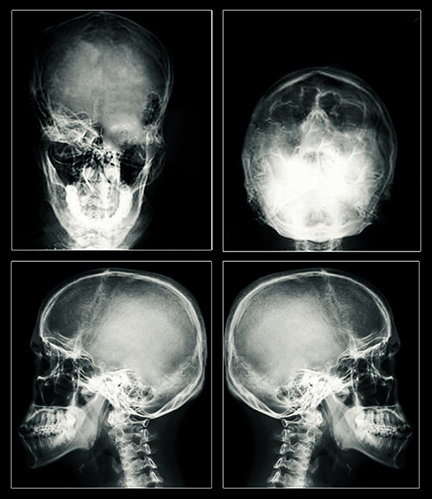

התוצאה נשארת בעינה: פרכוס גרנד מל ונזק מוחי, שיכול להיות תמידי. זרימת החשמל המוגברת היום במידה עצומה יכולה לקרוע חורים בתאי מוח ולהרוג את התאים. החשמל גם יכול להרוג את התאים על-ידי יצירת חום. בדיקות MRI שנעשו על מטופלים של ECT הראו צלקות וכיווץ של המוח – ראָיה חד-משמעית לנזק חמור.